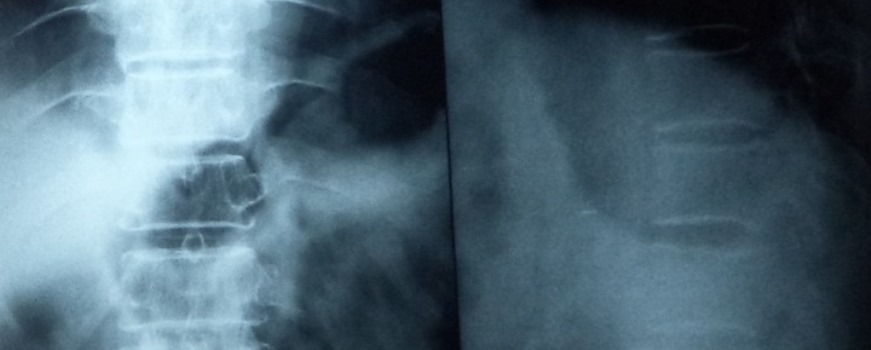

Some patients will get disc prolapse in cervical as well as lumbar regions. These intervertebral discs are soft shock absorbing materials in between the vertebra. Due to any acute strain, sports activities, weight lifting activities or during accidents these discs get injured and they prolapse or protrude into the vertebral canal.

This prolapsed disc will start compressing the spinal cord or nerve roots. So, this cord compression or root compression will cause neurological problems as well as intractable pain. To diagnose a disc prolapse we need to get an MRI of the affected region. If the disc prolapse symptoms are not relieved by conservative management then surgery maybe indicated. There are many types of discectomy or disc removal procedures available. Open techniques are time-tested and useful.